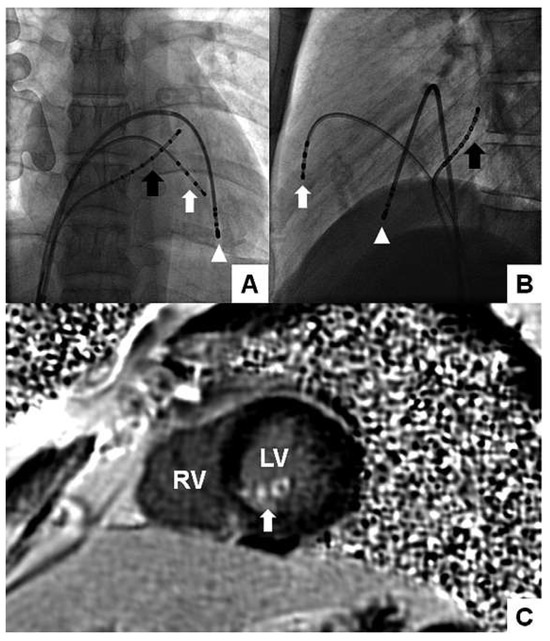

6 pages, 1978 KB

Article

Complex Percutaneous Coronary Interventions by Transradial Approach Using Sheathless Guiding Catheters

by Stephane Noble, Robert Francis Bonvini, Caroline Frangos, Pierre-Frédéric Keller and Marco Roffi

Cardiovasc. Med. 2012, 15(7), 218; https://doi.org/10.4414/cvm.2012.01682 - 29 Aug 2012

Cited by 1 | Viewed by 95

Abstract

Objective: To analyse our single centre experience with sheathless guiding catheters (GC) for complex percutaneous coronary interventions (PCI). Background: Failure of performing transradial approach (TRA) increases with the sheath size used, especially in cases of small and tortuous radial arteries. The [...] Read more.

Objective: To analyse our single centre experience with sheathless guiding catheters (GC) for complex percutaneous coronary interventions (PCI). Background: Failure of performing transradial approach (TRA) increases with the sheath size used, especially in cases of small and tortuous radial arteries. The use of recently developed sheathless GC may facilitate performance of TRA for complex PCI requiring large-lumen GC. Methods and results: We retrospectively analysed 20 consecutive patients who underwent complex PCI performed by TRA with a Sheathless Eaucath® GC (Asahi Intecc, Japan). The patients mean age was 68.9 ± 11.3 years. Indications for PCI were ST elevated myocardial infarction in 2 patients (10%), acute coronary syndrome in 4 (20%), and chronic stable angina in 14 (70%). Right TRA was used in all but one case. The 7.5-French (F) sheathless GC was used in all the procedures. Radial and brachial arteries crossing was possible in all cases with no associated procedural or GC-related complications. The number of vessels treated per patient was 1.30 ± 0.47 with 1.70 ± 0.92 stents implanted per vessel. The left main stem was the treated lesion in 9 patients (45%), 5 patients (25%) had complex bifurcation lesions and one (5%) had chronic total occlusion. The remaining 5 patients (25%) had severely tortuous and/or calcified coronary lesions. Rotablation was required in 2 procedures. Mean fluoroscopic time was 20.3 ± 7.5 min and mean volume of contrast media was 254 ± 83 ml. Conclusion: This preliminary experience in complex PCI, suggests that TRA using 7.5-F sheathless GC might be an attractive alternative to transfemoral access using 7-F conventional. Full article

Show Figures

Figure 1